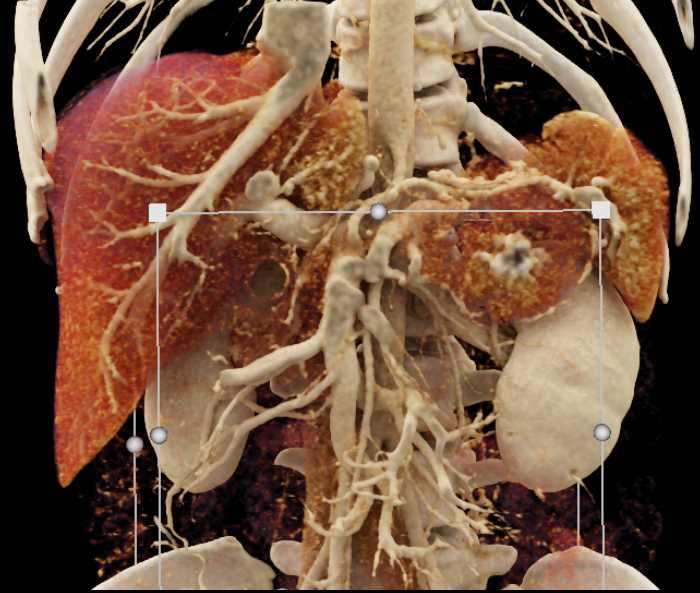

Neuroendocrine Tumor Pancreas